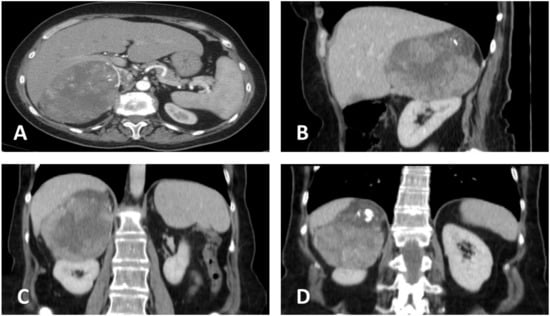

2. Case Presentation